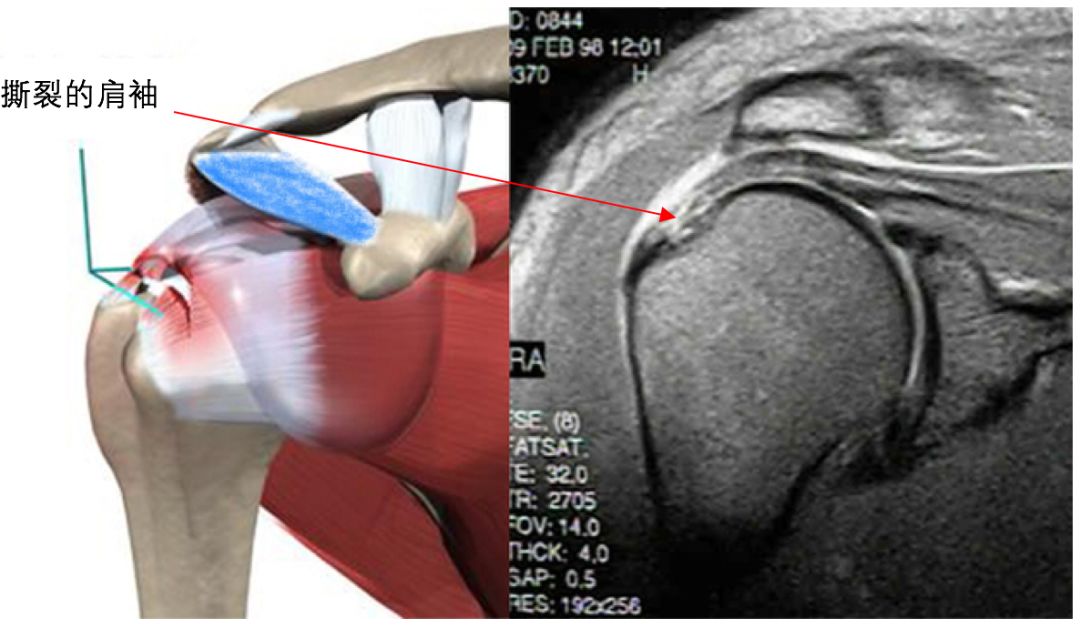

通常有经验的专科医生通过详细的查体,结合肩关节磁共振结果,都能对肩袖的损伤做出比较准确的诊断。

在MRI片在上只是显示肩袖的水肿,并没有明显的组织撕裂表现。只需停止损伤性运动,可以结合冲击波治疗、热敷、磁疗、短波治疗等手段,通常可以治愈。